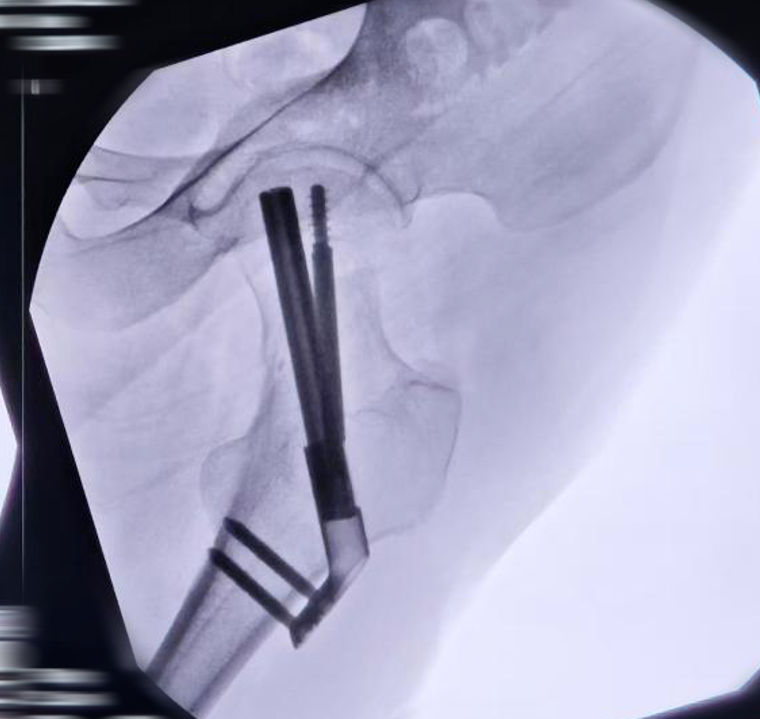

Surgical Technique Overview

1. Fracture reduction under imaging

2. Guidewire placement

3. Insertion of bolt and anti-rotation screw

4. Controlled compression fixation

image.pngimage.png